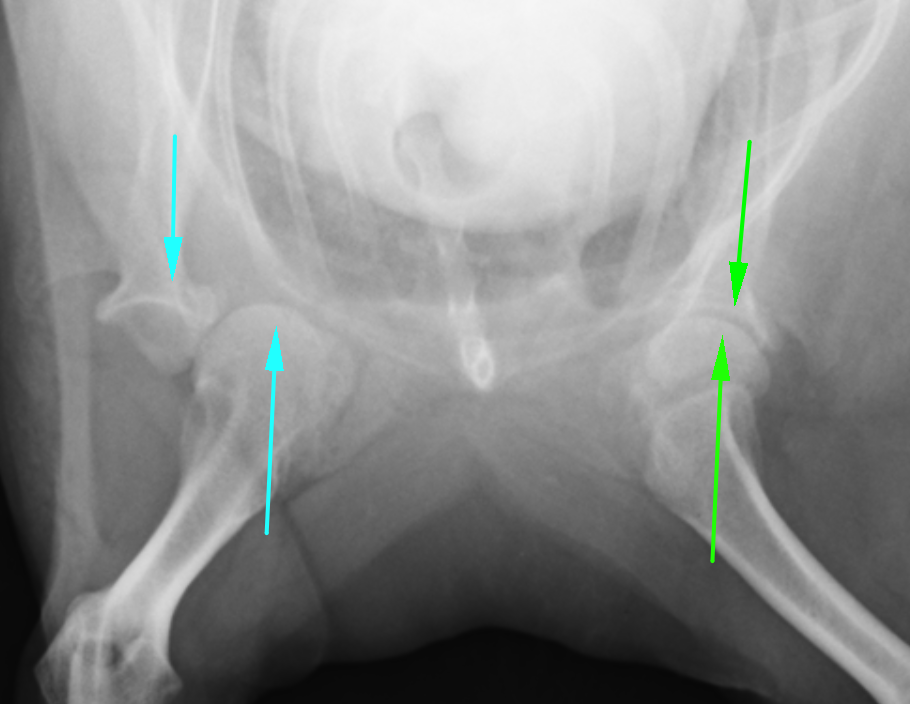

右肩関節脱臼のX線画像です。向かって左の青い矢印がずれているのがわかります。下の上腕骨が内側に入ってしまっているのです。正常な反対は緑矢印が合っているのがわかります。